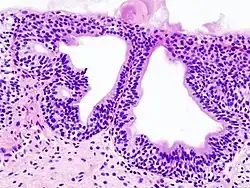

Cystitis glandularis is the transformation of mucosal cells lining the urinary bladder. They undergo glandular metaplasia, a process in which irritated tissues take on a different form, in this case that of a gland.[1] The main importance is in the findings of test results, in this case histopathology. They must distinguish a benign metaplastic change from the cancerous condition urothelial cell carcinoma.[2] It is a very common finding in bladder biopsies and cystectomies, and most often found in the trigone area. Cystitis glandularis lesions are usually present as small microscopic foci; however, occasionally it can form raised intramucosal or polypoid lesions. The cystitis glandularis lesions are within the submucosa.

Cystitis glandularis arises from and merges with Von Brunn's nests, which are groups of urothelial cells (cells of urinary tract) within the lamina propria and submucosa, formed from budding from the surface mucosa. They are considered normal. Cystitis cystica is a similar lesion to cystitis glandularis, where the central area of the Von Brunn's nests have degenerated, leaving cystic lesions. Other metaplastic entities in the urinary bladder include squamous metaplasia and nephrogenic adenoma.